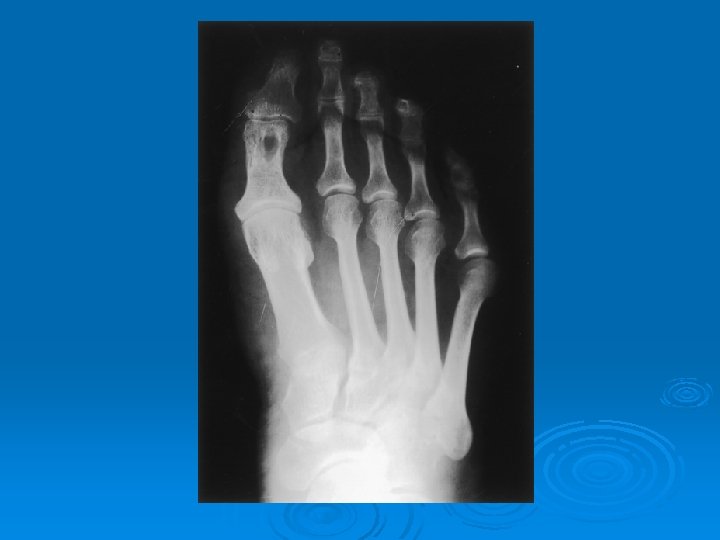

ELDE LİTİK LEZYONLAR